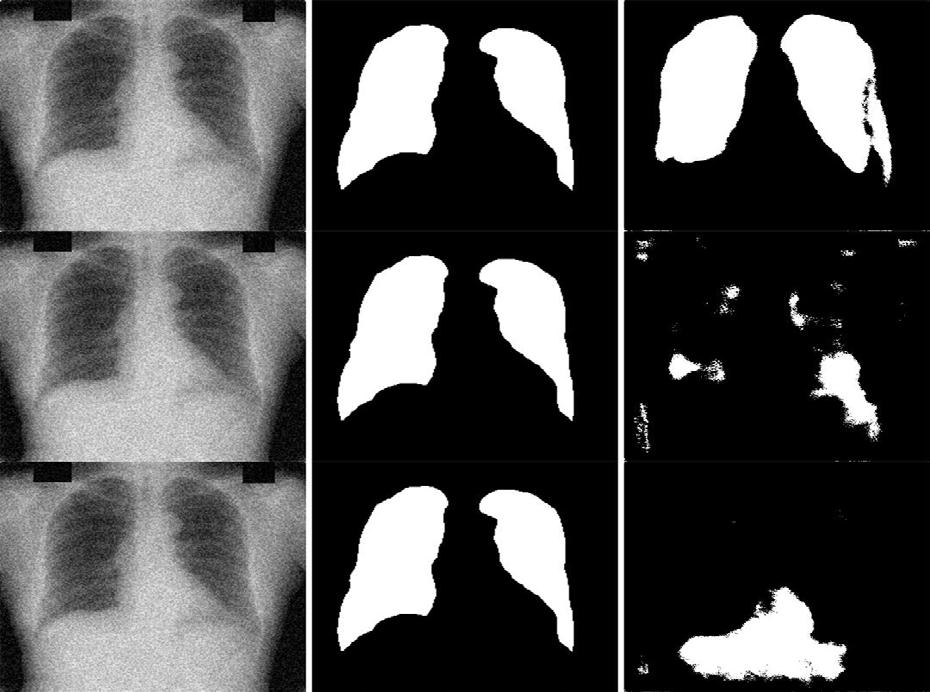

This performance of multi-stage transfer learning (MSTL) on a lung segmentation task within adverse conditions was investigated. It was concluded that most of the retrained models likely experienced covariate shifts with the exception of models trained on flipped datasets. This investigation gives insight into the thresholds of models trained on small datasets to perform under adverse conditions, adding to the knowledge base required to successfully integrate deep learning (DL) into the medical workflow.